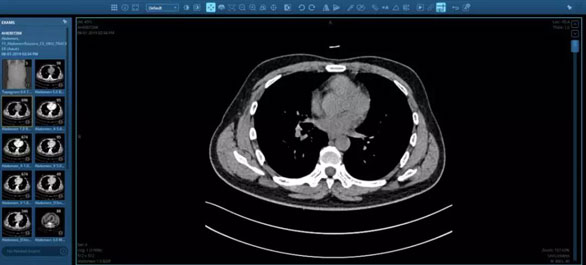

CT、MRI等醫(yī)學(xué)影像檢查正發(fā)揮著越來(lái)越重要的作用。有超過(guò)75%的患者在診療過(guò)程中需放射科醫(yī)生的幫助。但專業(yè)影像人才的培養(yǎng)速度遠(yuǎn)遠(yuǎn)趕不上需求增速,放射科醫(yī)生面臨著巨大缺口。

為此,一些公司開始探索運(yùn)用人工智能(AI)和計(jì)算機(jī)視覺(jué)技術(shù)輔助放射科醫(yī)生。

Aidoc的頸椎骨折和肺栓塞人工智能產(chǎn)品,分別獲得了FDA的批準(zhǔn)。臨床中頸椎損傷的遲發(fā)性或漏診發(fā)生率在5%到20%之間,頸椎骨折產(chǎn)品旨在幫助確定胸部CT掃描中肺栓塞的潛在病例,從而幫助醫(yī)生優(yōu)化工作流,讓臨床醫(yī)生優(yōu)先診斷高風(fēng)險(xiǎn)的患者。

而肺栓塞人工智能產(chǎn)品主要用于輔助臨床醫(yī)生診斷病人肺栓塞,并實(shí)現(xiàn)根據(jù)患者的危重性排序分類。Aidoc的肺栓塞解決方案榮獲2019年度“最佳放射軟件”Minnie獎(jiǎng)。